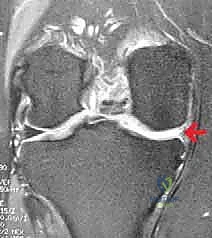

* الأشعة السينية (X-rays): بوضعيات خاصة (مثل Standing Rosenberg view) لتقييم المسافة بين العظام والتأكد من عدم وجود خشونة متقدمة، وكذلك صور الساق بالكامل (Long leg films) لقياس محور استقامة الساق.

* الرنين المغناطيسي (MRI): لتقييم حالة الغضروف المفصلي المتبقي، الأربطة، والتأكد من حجم الاستئصال السابق.